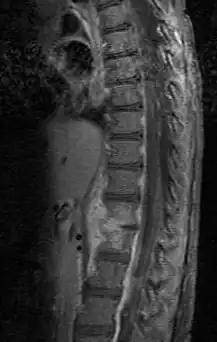

Die Labordaten können einen Hinweis auf einen entzündlichen Prozess liefern, können aber auch unauffällig bleiben. Im Röntgenbild erscheint das Bandscheibengewebe im späteren Stadium verdichtet, anfangs ist oft kein krankhafter Befund zu sehen. Aufschluss bringt oft das Kernspintomogramm, auch eine Computertomographie kann Hinweise liefern. Ein Erregernachweis gelingt unter Umständen durch Blutkulturen. Zusätzlich kann zur genaueren Bestimmung der Erreger eine Punktion durchgeführt werden.